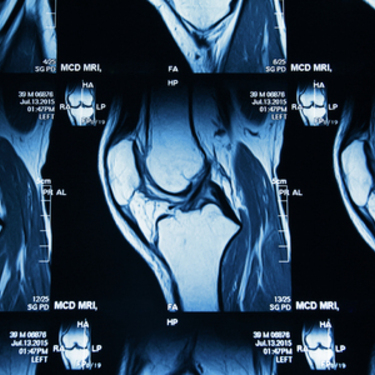

Facts: Isa Dean underwent a magnetic resonance imaging scan in 2006 that showed degenerative changes in her lumbar spine.